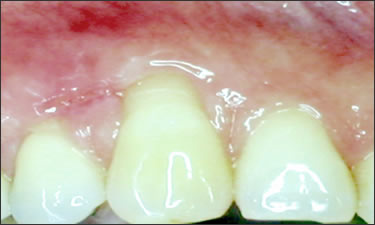

This mouth had recession on just one tooth with very little bone to support the tooth. The area needed support and thickness. The tissue was placed and the area now has thicker tissue to withstand the forces that the patient needs to place on it.